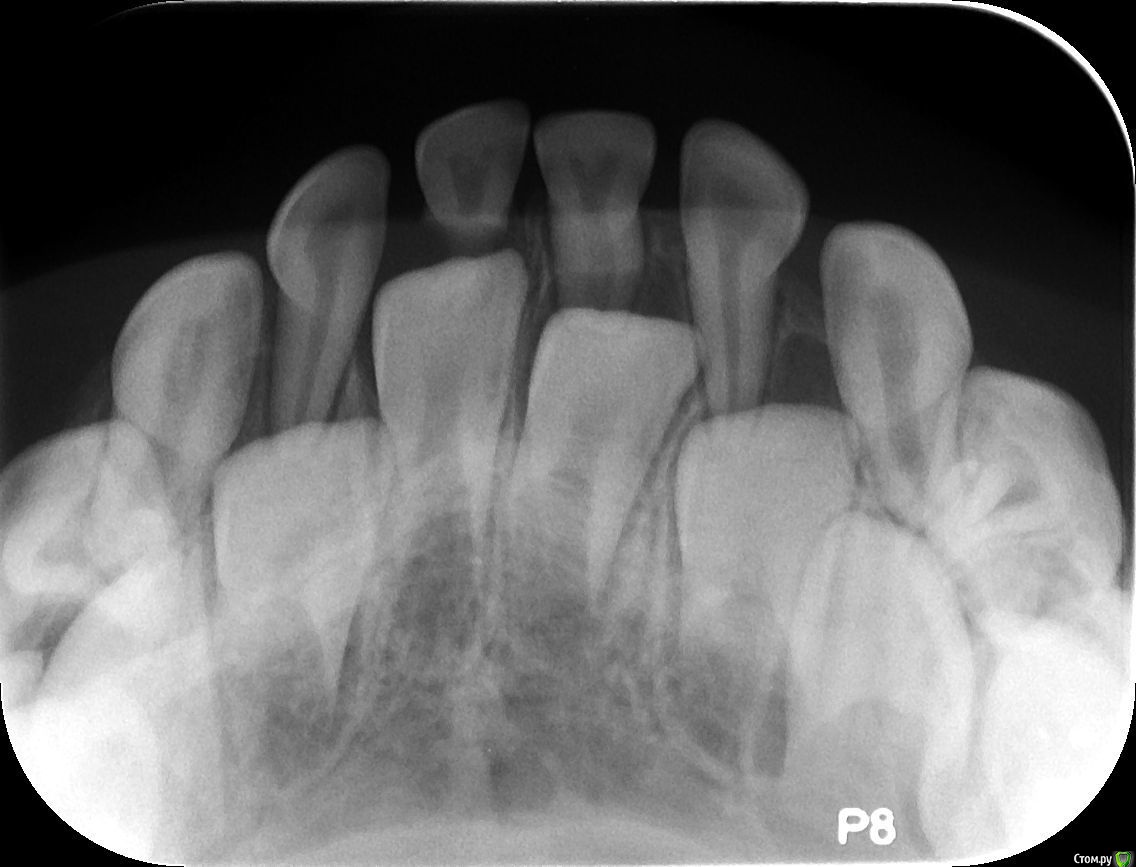

Elena Bundren Опубликовано 27 июня, 2018 Поделиться Опубликовано 27 июня, 2018 Здравствуйте!Пришли с 5-летним ребенком к стоматологу. Он обнаружил 12 кариесов, сказал, на несколько зубов надо ставить серебренные коронки.Моляр справа внизу подлежит удалению, так как под ним инфекция.И все это хорошо бы сделать под общей анестезией за один раз.Вопросы уважаемым докторам, сколько, по-вашему, зубов реально подлежит лечению, и есть и возможность, на ваш взгялд, сохранить моляр, если да, то какое нужно лечение.Также, каково ваше мнение об общей анестезии для ребенка 5 лет. Ссылка на комментарий

St. Опубликовано 27 июня, 2018 Поделиться Опубликовано 27 июня, 2018 Добрый день. Зубы действительно в очень плохом состоянии и практически на всех между зубами есть кариес.Металлические коронки у детей это хорошо, они позволяют надежно провести лечение сильно разрушенных зубов и не опасаться сколов и вторичного кариеса. Ссылка на комментарий